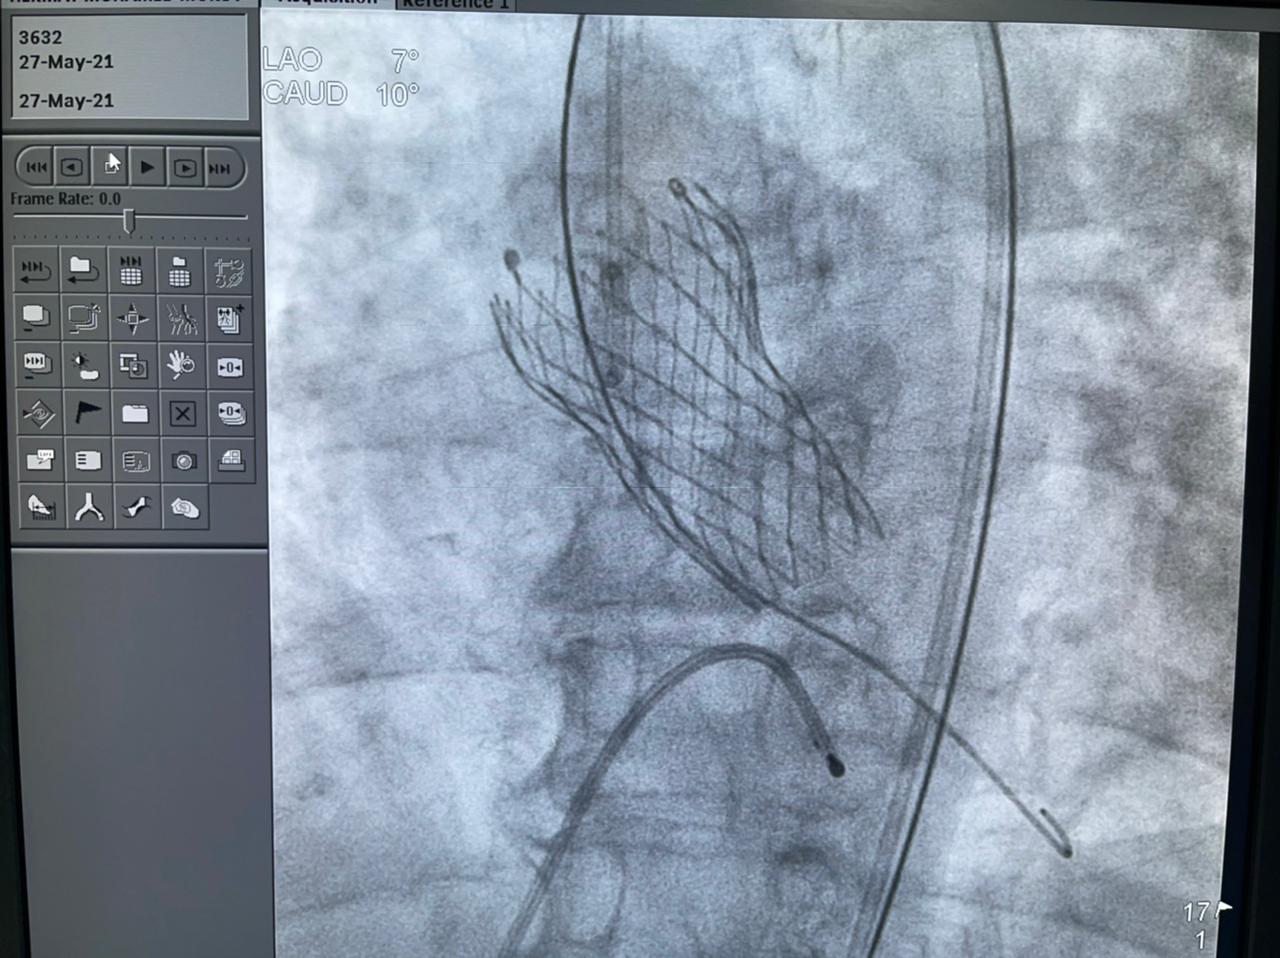

وأضافت الهيئة أن الحالة الثانية هي عملية زراعة الصمام الأورطي لمسنة تبلغ من العمر 78 عامًا، كانت تعاني من ضيق شديد بالصمام الأورطي، وتمت العملية بنجاح بعد أن كانت تعاني من تعب شديد وضيق بالتنفس وآلام بالصدر ونوبات إغماء، وتم إقرار علاج المريضة بعملية زراعة الصمام نظرًا لتقدم عمرها والضعف العام لحالتها الصحية، وتم إجراء العملية بتقنية التافي العالمية التي يتم بها تغيير الصمام الأورطي عن طريق القسطرة.

وتابعت الهيئة أنه قام بإجراء العمليات للمرضى الثلاثة في يوم واحد، فريق من أمهر الأطباء الأخصائيين والاستشاريين في علاج أمراض القلب والقساطر القلبية، يضم، الدكتور طارق رشيد أستاذ القلب والقسطرة وخبير حالات الانسداد المزمن للشرايين التاجية ورئيس قسم القسطرة القلبية بمستشفى النصر التخصصي، والدكتور ياسر صادق استشاري القلب وخبير القسطرة القلبية، الدكتور أمير البسطويسي استشاري جراحة القلب والصدر، الدكتور أحمد شبل استشاري القلب والقساطر التداخلية، الدكتور محمد علم الدين استشاري القلب والقسطرة العلاجية، الدكتور محمد لبيب استشاري جراحة الأوعية الدموية، وإخصائي علاج أمراض القلب والأوعية الدموية الدكتور معتز سلامة و الدكتور محمد عطا، أخصائي علاج أمراض القلب والقسطرة العلاجية الدكتور مصطفى رفعت، الدكتور أحمد عبد الرؤوف أخصائي التخدير بالمستشفى.

ومن جانبه أكد الدكتور طارق رشيد أن ما يحدث في قسم القلب بمستشفى النصر إنجاز يتفوق على النسب العالمية خاصة في مجال القساطر التداخلية، منوهًا أن الهيئة العامة للرعاية الصحية تعمل في الفترة الحالية على توثيق تلك الأرقام بصورة علمية بحثية على المستوى العالمي لتوضيح الإنجاز الكبير الذي يحدث في جراحات القلب بالهيئة.

كما أشار الدكتور ياسر صادق إلى أن مصر أصبح لديها كفاءات بشرية، ولديها تقنيات وأجهزة تمكن من إجراء أصعب العمليات الدقيقة في مجال القلب، والتي من بينها عملية التافي، وذلك بمعايير عالمية تضاهي وتتفوق على الأرقام العالمية في المجال.